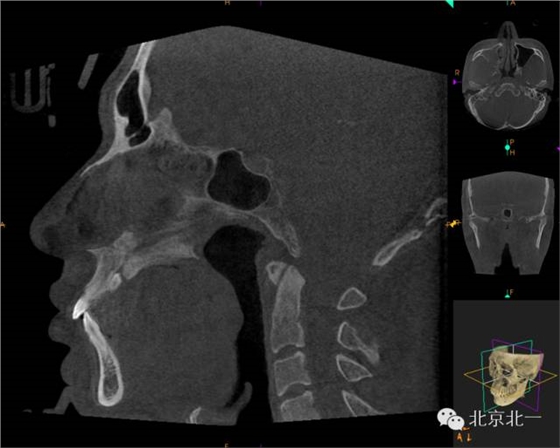

CBCT顯示埋伏多生牙位于腭側(cè)高位,接近切牙管開口位置。

CBCT矢狀位顯示多生牙倒置阻生,位于鼻腭神經(jīng)管口